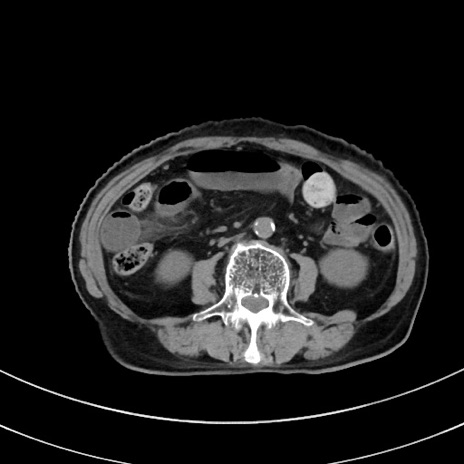

冠状断像

症例33(横断像)

【症例】70歳代 女性

【主訴】心窩部痛

【現病歴】延髄病変の精査・加療にて神経内科入院中。本日より心窩部痛あり。

【既往歴】虫垂炎

【身体所見】右下腹部を中心に圧痛と反跳痛あり。

【データ】WBC 10900、CRP 0.02